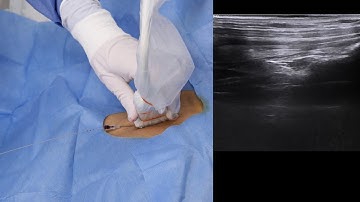

Central Line placement: Subclavian Vein Approach